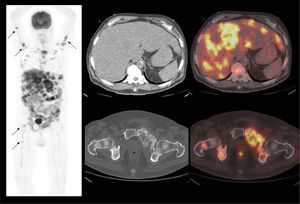

En cáncer vesical con invasión muscular, las metástasis ganglionares y a distancia son de alta frecuencia (Figura 6). En un grupo de 150 pacientes en etapa pT2-4, Shinagare et al (14) describieron un 69% de compromiso secundario ganglionar, 47% óseo, 37% pulmonar, 26% hepático y 16% peritoneal.

Un tema de especial interés es entonces la ocurrencia de metástasis a distancia, ya que pueden cambiar radicalmente el manejo de los pacientes, especialmente la posibilidad de optar o no a cirugía curativa. Ya que las lesiones secundarias óseas son las más frecuentes, es mandatorio optimizar su detección. El PET/CT presenta varias ventajas en esta materia, ya que tiene alta sensibilidad en lesiones líticas, de alta frecuencia en estas neoplasias, y permite evaluar conjuntamente esqueleto axial y apendicular, ya que las metástasis a huesos largos no son poco frecuentes en estas neoplasias (14,20) (Figura 6).